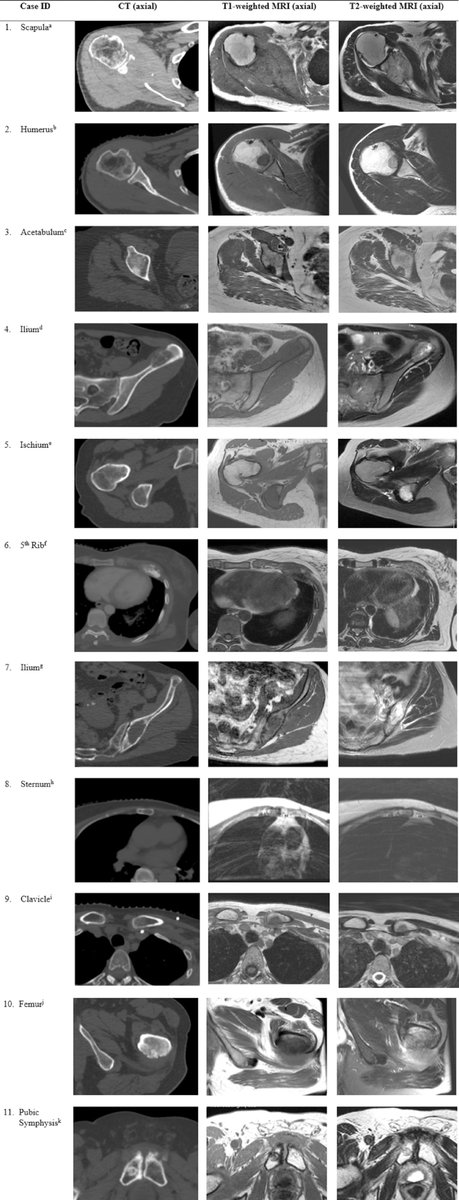

#RedJournal Article: International Multi-institutional Patterns of Contouring Practice and Clinical Target Volume Recommendations for Stereotactic Body Radiotherapy for Non-Spine Bone Metastases. @TimKWin ➡️bit.ly/Nguyen_RedJ

Marginal failures after bone SBRT is a thing! This guideline may help target delineation bit.ly/3v85Kfl - 11 cases, 9 #radonc contours international effort 🇨🇦🇺🇸🇨🇭🇦🇺🇰🇷🇳🇱. Suggest a 5mm-10mm intraosseous margin for microscopic disease. Extraosseous margin for cortex breach